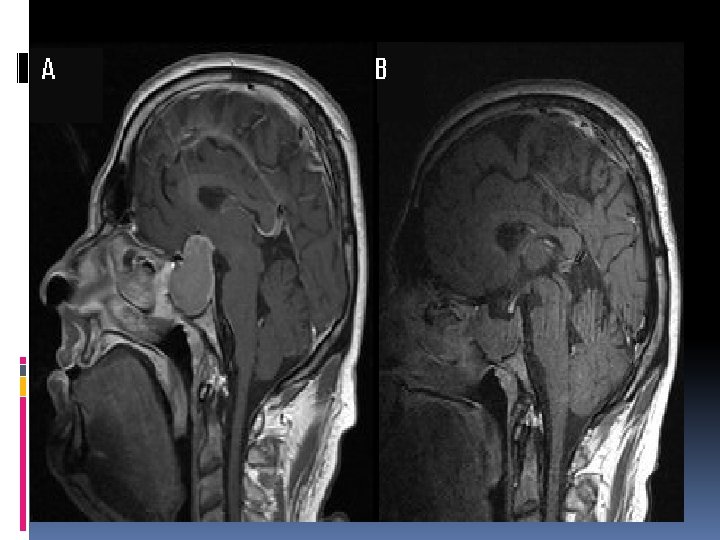

craniophryngioma Arise from anterior superior margin of pituitary gland. Lined by stratified squamouse epithelium All CP had solid and cyctic part, contain cholestrol crystal (machine oil) CP donot undergo malignant degeneration but malignant behaviour, difficult cure (C. P adherant to the major art. At the base of the brain(int. carotid)

craniophryngioma Calcification in plain x ray 54% in childhood , 20%, in adult , 2. 5 -4 % of all brain tumor 9% of children brain tu. , peak incidence age 5 -10 year 55 -85% five years survival rate 5 -10 -% mortality due to hypothalamic injurey High recurrence rate in 1 st 1 -3 years

Signs & symptoms Symptoms Headache, nausea &vomiting, visual loss, short stature, mental problems, diplopia Signs Papilledema , visual defect, endocrine dysfunction, cranial nerve palsy, psychatric abnormality

Management Diagnosis Plain x-ray, C. T , M. R. I, endocrine assessment Treatment Surgery(hydrocephalus, cyst drainage) Medical replacement(steroids, A. D. H replacement with fluid) Radiotherapy(better results in children than adults)